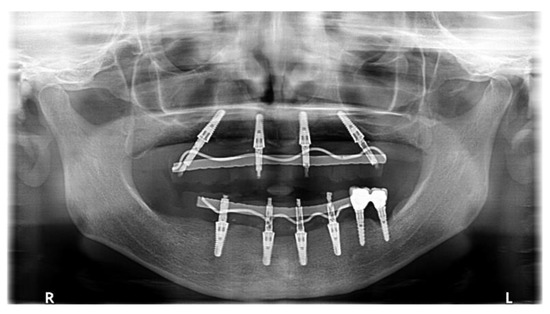

Figure 3. Panoramic view at 7-year after loading. Both protheses were replaced by monolithic ones in the prosthesis recall program.